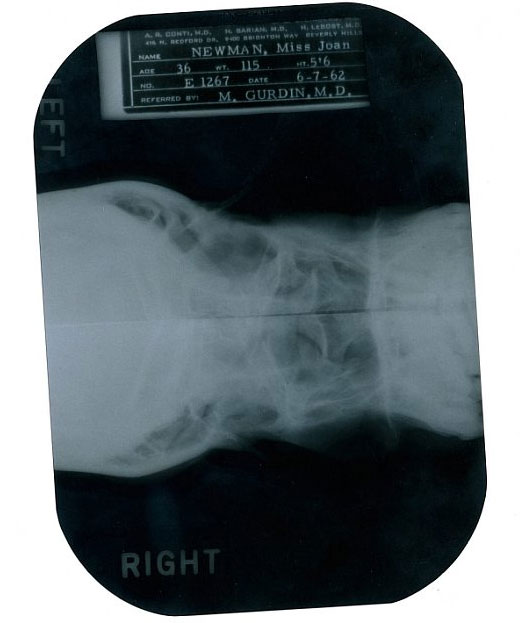

Las notas escritas por el Dr. Michael Gurdin comenzaron en 1958, cuando la actriz lo consultó por una "deformidad en el mentón". Aquí figura con su nombre de casada, Marilyn Miller, ya que había contraido matrimonio con el escritor Arthur Miller.

A las reveladoras notas escritas por el médico Michael Gurdin, supuestamente encargado de llevar a cabo la operación quirúrgica en 1950, se suman varias pruebas de rayos X realizadas el 7 de junio de 1962, dos meses antes del fallecimiento de la artista, en las que se pueden apreciar desde diferentes ángulos los huesos faciales de Marilyn, sus conductos nasales y su paladar.

Radiografías de Marilyn Monroe, bajo el nombre de Marilyn DiMaggio, sacadas por un joven médico en 1954.